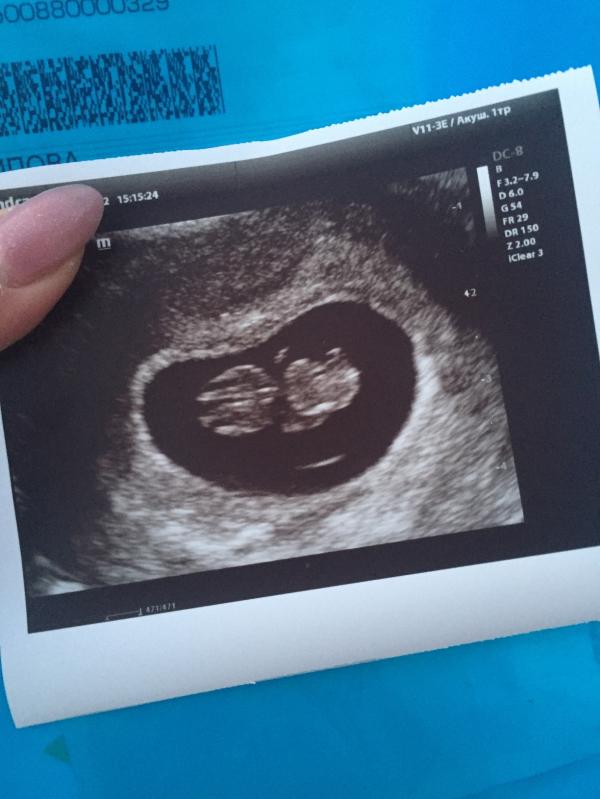

Узи показало, что все хорошо на сроке 8,3 недели - ждем скрининг!

Сходила сегодня на узи😍Все у нас хорошо,дали послушать сердцебиение ,все отлично ,анализы хорошие 🙏🏾Встала на учёт сегодня 🥳Срок у нас 8,3🙏🏾Ждём направление на первый скрининг 🥰🙏🏾